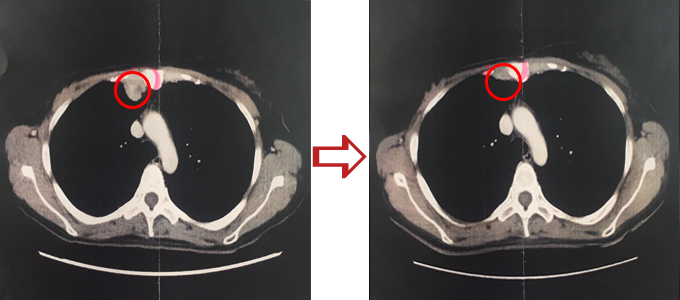

肺癌、抗がん剤治療後、再発

横内漢方治療前と後